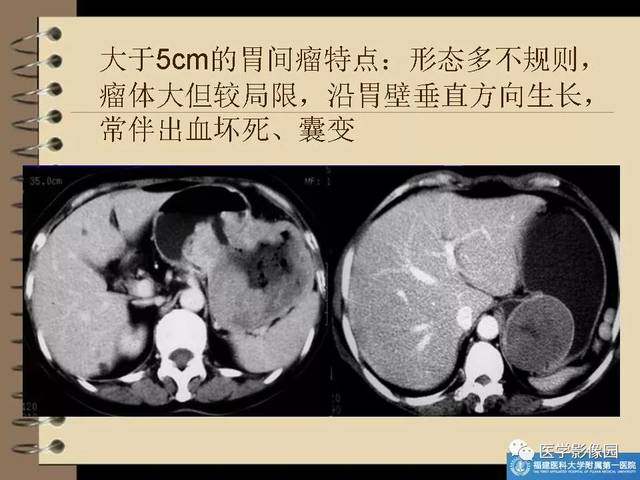

3、爸爸得了胃部恶性间质瘤,但切除下来的瘤里面有坏死现象,这样是不是好…

这个病一定要坚持锻炼,但是一定不能累。有计划的运动有助于恢复体能,提高抵抗力。胃肠道间质瘤目前有特效药,格列卫。你可以用它。坏死和有丝分裂都是恶性的证据。肿瘤坏死是某些食物和药物中肿瘤坏死因子的结果。如果自身免疫系统的免疫细胞能及时清理这些坏死组织,肿瘤就会消散。这是一个好现象。不要急着干重体力活。建议按照以下饮食计划来管理自己的饮食。